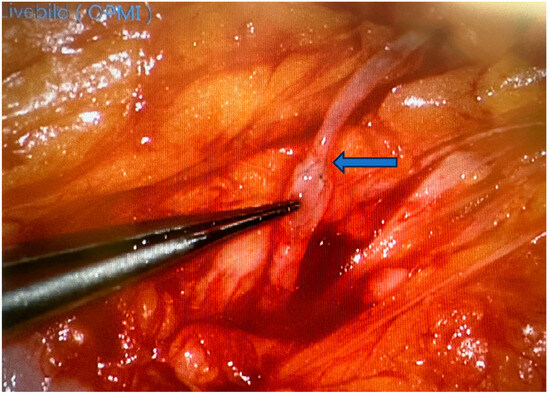

3.2. Advances of Nerve Bridging and Transfer